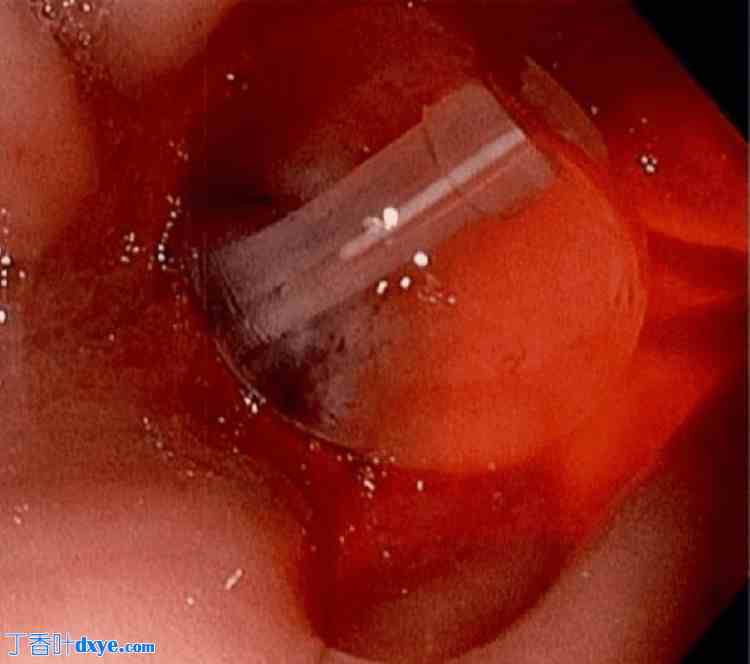

术后第 3 天进行的食管胃十二指肠镜 (EGD) 检查显示整个胃黏膜充血,可见胃管进入胃体前壁并从胃后壁穿出,入口和出口周围可见清洁溃疡(图 2)。这被推测是胃肠道出血的原因。患者接受泮托拉唑 40 毫克静脉注射 (IV),每日两次,持续三天,然后改为每日一次。联系外科医生对错位的胃管和后壁胃造瘘部位进行手术处理。诊断性腹腔镜检查于同日进行,未发现腹腔内污染迹象。腹腔镜操作/旋转胃部操作显示胃管已从胃后壁伸出(图3)。经皮牵拉胃管,将胃管重新置入胃内,并使用内镜胃肠道吻合器从浆膜处缝合缺损。通过注射和抽吸生理盐水以及术中胃镜检查(EGD)确认胃管位置(图4),然后关腹。患者可耐受管饲,无并发症,两天后出院。

图2. (A-B) 食管胃十二指肠镜检查结果显示,胃造瘘管位置异常,进入胃前壁,并从胃后壁伸出,双侧胃壁黏膜均有清洁的管周溃疡。